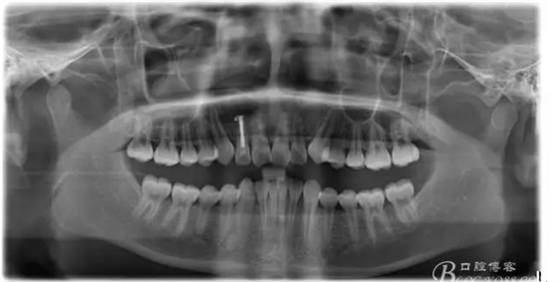

圖17. 術(shù)后的全景片影像: